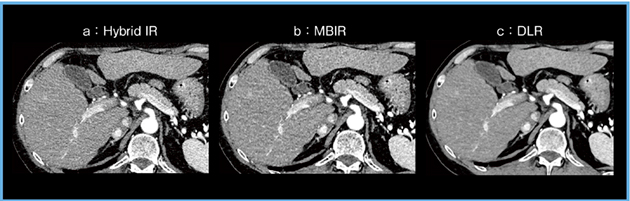

胸部CT(肺野)においては,MBIR画像はFBP画像やHybrid IR画像と比較して,空間分解能が高く,ノイズも低くなり,有用性が高いと報告されている4)。しかしながら,腹部CTに各画像再構成法を適用してみたところ, Hybrid IRと比較してMBIRの画質が向上しているとは言いがたい画像となった(図1)。実際に腹部CTではMBIRを適用しても,特に線量が十分でない場合には低コントラスト病変の検出能が向上しないことが報告されている5)。

そこで,腹部CTの画質改善に期待されるのが人工知能(AI)である。高品質なCT画像(高線量,理想的な条件のMBIR)を教師にして学習したAIを用いれば,腹部CTの画質を改善できると考えられ,開発されたのがDLRのAiCEである(図2)。

図1 腹部CT:画像再構成法による比較